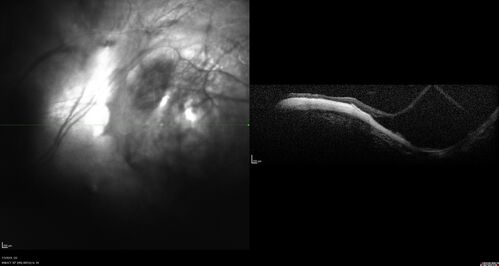

Staphyloma and Atrophy with Vitreoretinal traction

Only eye of patient with Albinism and decreasing vision now 5/200 in this 72 year old man. There is myopic tractional maculopathy. The patient also has albinism by history.